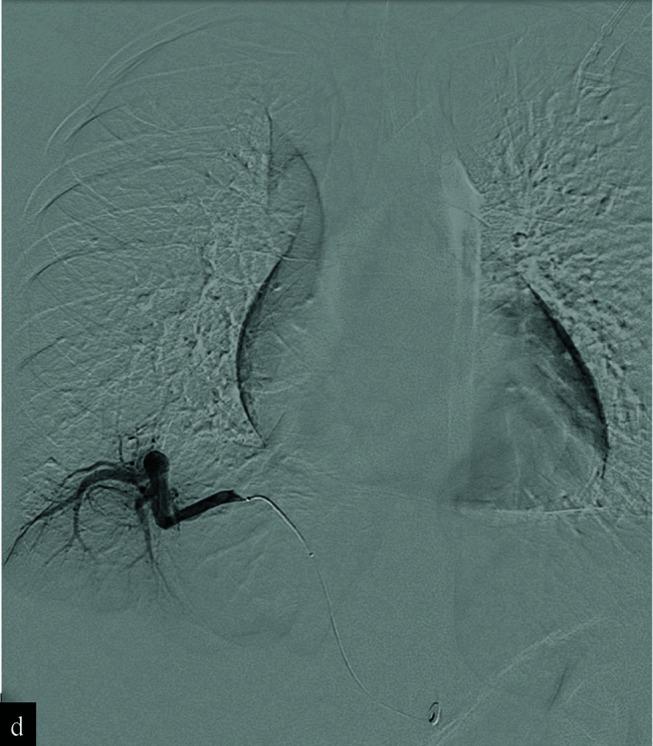

Successful coil embolization of pseudo pulmonary sequestration: A report of two cases.

Pseudo pulmonary sequestration is a rare congenital anomaly, which entails systemic arterial supply to the basal segment of the lung in the absence of pulmonary arterial supply. Diagnosis is often made by radiographic appearance without specific clinical symptoms. The mainstay treatment is surgical resection; however, embolization can be considered as an alternative approach. Herein, we present a report of two females who presented with nonspecific chronic chest pain. Both patients were diagnosed with pseudo pulmonary sequestration on CT scan and completed uneventful pregnancies prior to successful management with coil embolization.